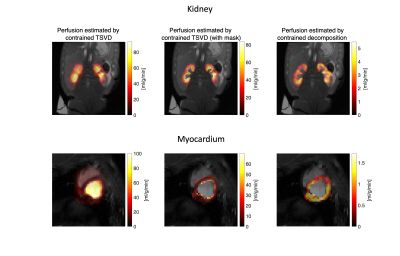

The simulation setup and results are shown in Figure 1 and 2. The absolute error and standard deviation of the constrained decomposition method is 10 times smaller than the constrained TSVD method (Figure 2). Figure 3 shows the performance in vivo. In both, the proposed method can separate perfusion and AIF components. Figure 4 shows the in vivo comparison of the two methods. In both in vivo cases, the perfusion estimated by constrained TSVD is higher near the arteries compared to the proposed method. The normal perfusion values in a pig are around 3ml/g/min in the kidney and 2 ml/g/min in the myocardium7,8. Compared to the reference value, the constrained TSVD method has a perfusion value of around 80 ml/g/min near the arterial characterized by the AIF component, whereas the proposed method has a perfusion value of around 4 ml/g/min. So far, the proposed method is only designed and tested for healthy myocardium described by a single signal component. For myocardial ischemia, several myocardial components may need to be added and constrained, to sufficiently describe variation in bolus arrival timing.

Figure 4. Comparison of constrained TSVD and the proposed decomposition method in vivo. Constrained decomposition separates components to reduce partial volume effects. In both kidney and myocardium, constrained TSVD gives abnormally high perfusion estimates compared to reference values7,8